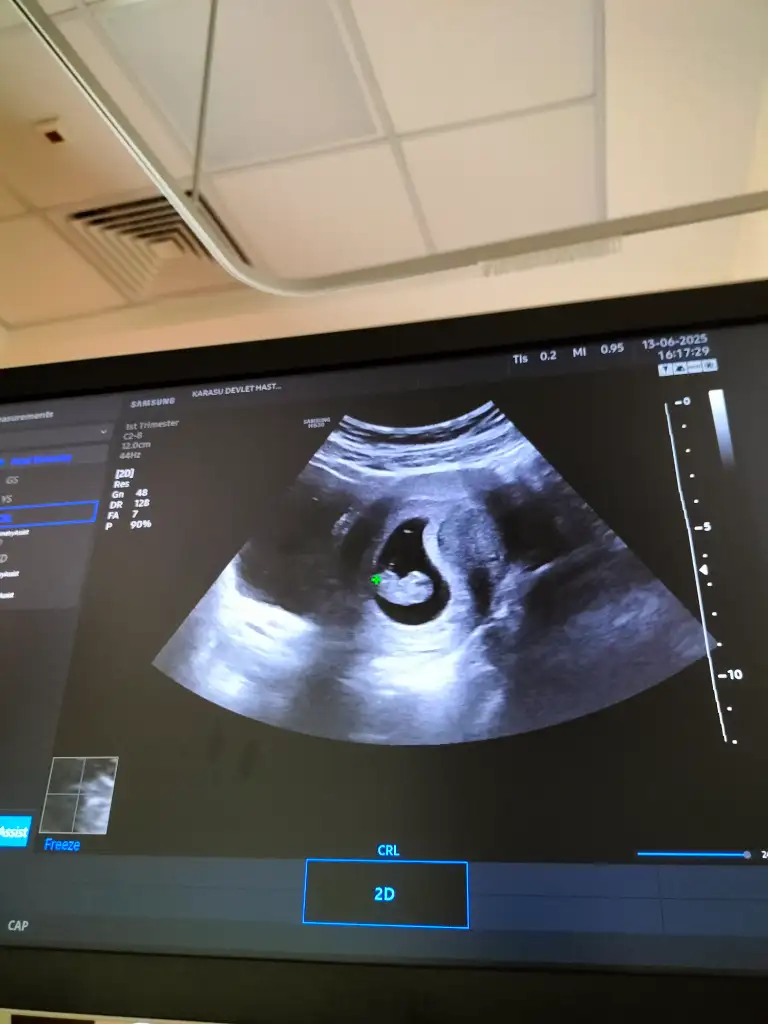

Hemen sana bilgilerimi veriyorum. Son kontrolde kalp atışı duyuldu ama çok minik.6+6 sat a göre. Bebek 5+6 ölçüldü CRL 3.06mm.İnşallah öyledir canım, sağlıkla alırsın inşallah kucağına. Kesen kaç mm boyutundaydı hatırlıyor musun? Bana da %99 boş deyince dünyam tersine döndü, ne yapacağım bilmiyorum. Böyle bir şey olmasa bu kadar kesin konuşur muydu?